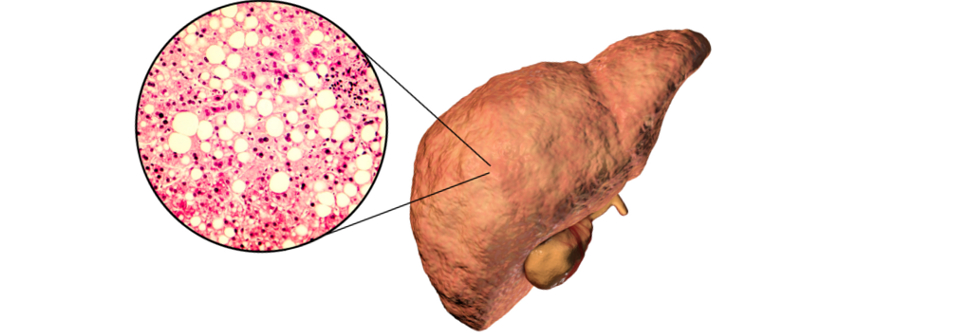

Menschen mit Typ-2-Diabetes neigen dazu, eine nicht-alkoholische Fettleber (NAFLD) zu entwickeln. Umgekehrt ist NAFLD mit einem zweifach erhöhten Risiko für einen Typ-2-Diabetes assoziiert. Verlieren Patienten an Gewicht, können sie damit auch ihre Fettleber verringern – in der Praxis ist dies in vielen Fällen aber nur schwer zu erreichen.

Es gibt jedoch Hinweise, dass sich SGLT2-Hemmer dafür eignen könnten, eine NAFLD zu behandeln. In einer randomisierten Phase-4-Studie untersuchten die Forscher um Dr. Sabine Kahl vom Deutschen Diabetes-Zentrum (DDZ) an der Heinrich-Heine-Universität Düsseldorf gemeinsam mit Wissenschaftlern des…